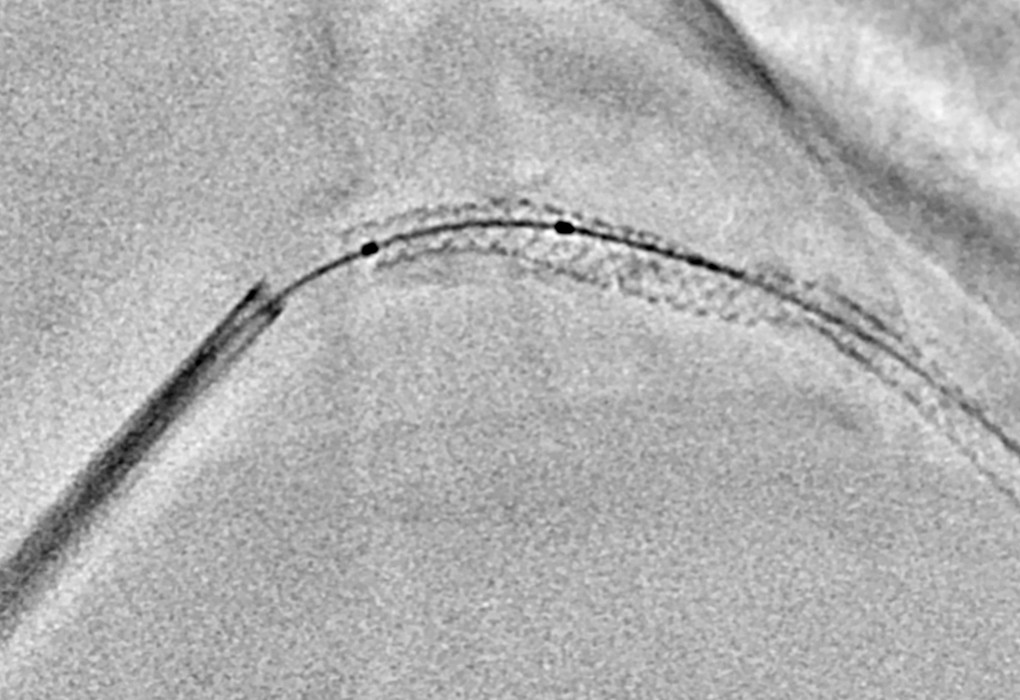

平板在一定程度上确定下来后,接下来针对PCI的应用程序不断进步。在所有器材的进化当中,DES的支架梁也变薄了,随之可识别性变差了。其中,其他设备上虽然也出现了突出支架的应用程序,但是处理需要时间,另外,所得到的图像有的也仅仅是静止的画面,询问过其他医院机构,据说他们也几乎不怎么使用。于是,云顶国际开发了实时的StentView,以此为契机,支架突出应用程序的话题也增多了。我想也正因为它是实时的才会被广泛使用。对于心脏来说,时间决定成败。

StentView的可识别性如何呢?从unity edition开始,显示由3分成变成了全屏显示。

- 安藤

- 可识别性非常好,能够清晰地实时看到支架。虽然刚开始使用的时候有些不习惯的地方,但是现在完全没有违和感。

- 曾我

- 我觉得与之前的版本相比,质量得到了提升。

- 支架的扩张不良之类的,支架梁的每1根都能看到。能够清楚地看到这里是否狭窄之类的情况。

- 一之濑

- StentView中,存在多个器材的情况下,有能够通过ROI来设定标记检出区域的功能,这个也非常不错。虽然需要稍微习惯一下,但使用起来非常好用。尤其是在动作大的右冠状动脉的1~2号区域,设定ROI的效果显著,能够更加准确地获得优质的图像。